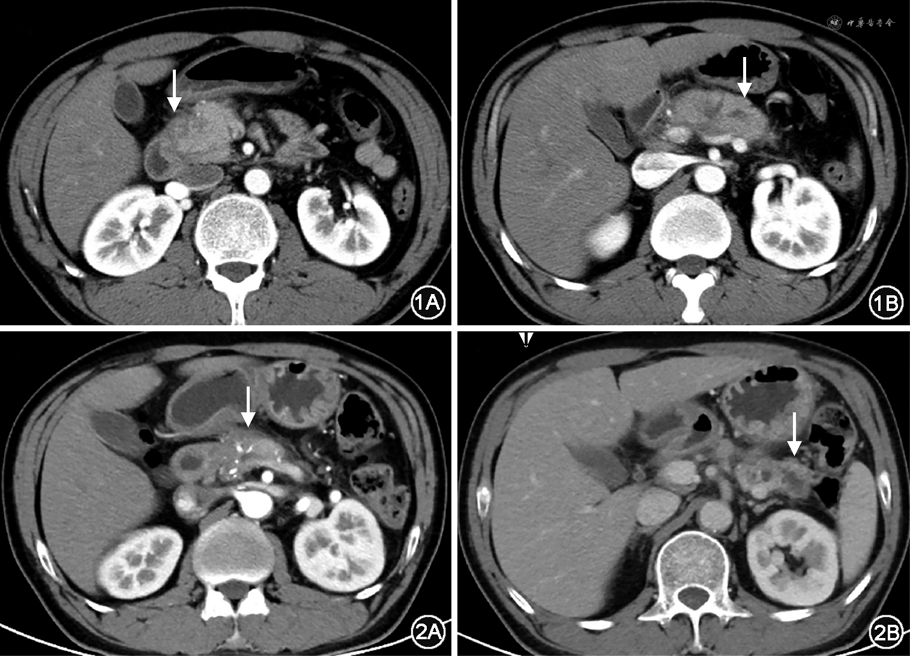

患者男性,50岁。因乏力伴血糖升高15年、腹泻近2年于2022年6月就诊北京协和医院内分泌科。2007年患者无诱因出现乏力,就诊外院发现血糖升高(具体不详),否认多饮、多尿、口干及体重下降,病初体重约75 kg(体重指数25.35 kg/m2),饮食控制不佳,喜饮酒;当地医院诊断为“2型糖尿病”,予二甲双胍及预混胰岛素(具体剂型及剂量不详)治疗,监测空腹血糖(FBG)8~10 mmol/L,餐后血糖(PBG)12~19 mmol/L,乏力较前好转,否认低血糖及糖尿病酮症酸中毒(DKA)症状。后自行停用二甲双胍。2009年患者因血糖控制不佳,调整治疗方案为:三餐前门冬30胰岛素+睡前甘精胰岛素皮下注射(剂量不详,偶有漏打),监测FBG 4~6 mmol/L,餐后2 h血糖(2hPBG)7~10 mmol/L,外院查空腹C肽0.23 nmol/L,餐后C肽0.93 nmol/L。2012年起患者每年数次于进食油腻食物后出现急性上腹痛,外院胰腺CT考虑急性胰腺炎(图1),均予保守治疗后好转,监测血糖大致同前,体重无明显变化。2020年7月再次于进食油腻饮食后出现上腹部剧痛,伴恶心、呕吐,胰腺增强CT诊断胰管结石、急性胰腺炎(图2),行胰十二指肠切除术(pancreaticoduodenectomy,PD)(胰头部切除)+胰管取石术。病理:慢性胰腺炎,伴部分腺体萎缩,间质显著纤维化和玻璃样变,可见胰管明显扩张,伴多发结石形成,周围淋巴结呈反应性增生。术后出现重度腹泻,频率可>10次/d,进餐后加重,便中可见未消化的食物残渣及油滴,无黏液、脓血,否认明显臭味,术后未再出现腹痛、呕吐。术后1个月内体重下降11 kg(75 kg➝64 kg),此后2年内进行性下降约11 kg(64 kg➝53 kg)。长期站立后易出现双下肢可凹性水肿,偶伴眼睑水肿,平卧休息可缓解。术后调整降糖方案为三餐前门冬胰岛素6、6、6 U+睡前甘精胰岛素12 U,监测血糖波动较大:腹泻稍轻时(6~8次/日)FBG 5~8 mmol/L,2 h PBG 8~12 mmol/L;腹泻较重时(10余次/日)自行停用胰岛素,血糖波动大(1.9~29 mmol/L),频繁于饥饿或腹泻后出现低血糖发作,进食后缓解。2022年1月,患者出现双小腿及足部麻木、脚踩棉花感,偶有过电样疼痛,血糖水平基本同前。2022年6月就诊本科门诊,考虑术后合并胰源性糖尿病,予胰酶肠溶胶囊150 mg、每日3次,腹泻减少为每日6~8次,便中油滴明显减少,为进一步诊治收入院。病程中,患者否认视物模糊、明显泡沫尿、肢端溃疡、偏身出汗等。否认糖皮质激素及干扰素长期应用史;无脸变圆红、皮肤紫纹,无面容改变、手足增大,无皮肤游走性红斑。精神、睡眠差,情绪略焦虑,食欲尚可,近半年每日主食约200~300 g,肉类及水果较少;近半年体重稳定,大便如上述,小便正常,夜尿0~1次。既往史:否认高血压、冠心病史,因胰管结石行手术治疗,术中输血2 600 ml。个人、婚育史:20余岁起,每日饮白酒约250~500 g、每日吸烟20~40支;配偶及2个女儿体健。家族史:否认胰腺炎、糖尿病家族史。